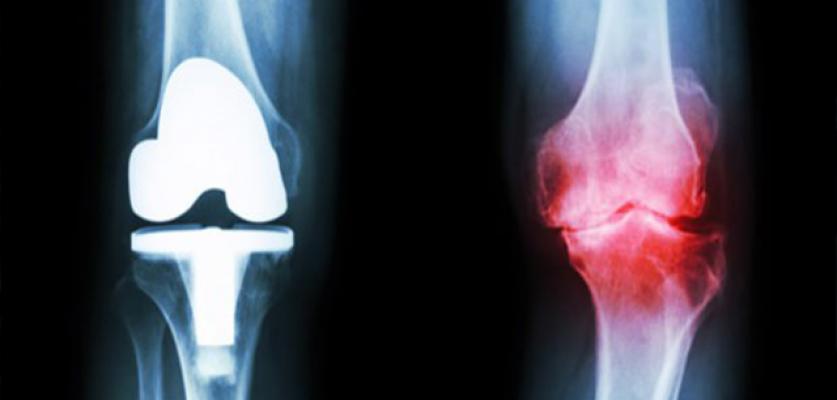

Birçoğumuz dizden veya farklı eklemlerden gelen çıtırtı seslerine aşinayızdır. Bu sesler tek başlarına bir hastalığın habercisi sayılmasa da eklem kireçlenmesinin ileri safhalarında ağrılara sebep olabilir. Eklem hareket açıklığı azalmadan evvel eklem çevrelerinde gördüğünüz şişlik, kızarıklık veya hareket esnasında açığa çıkan ağrı gibi durumlar görüyorsanız bir uzmana danışmakta geç kalmayın.